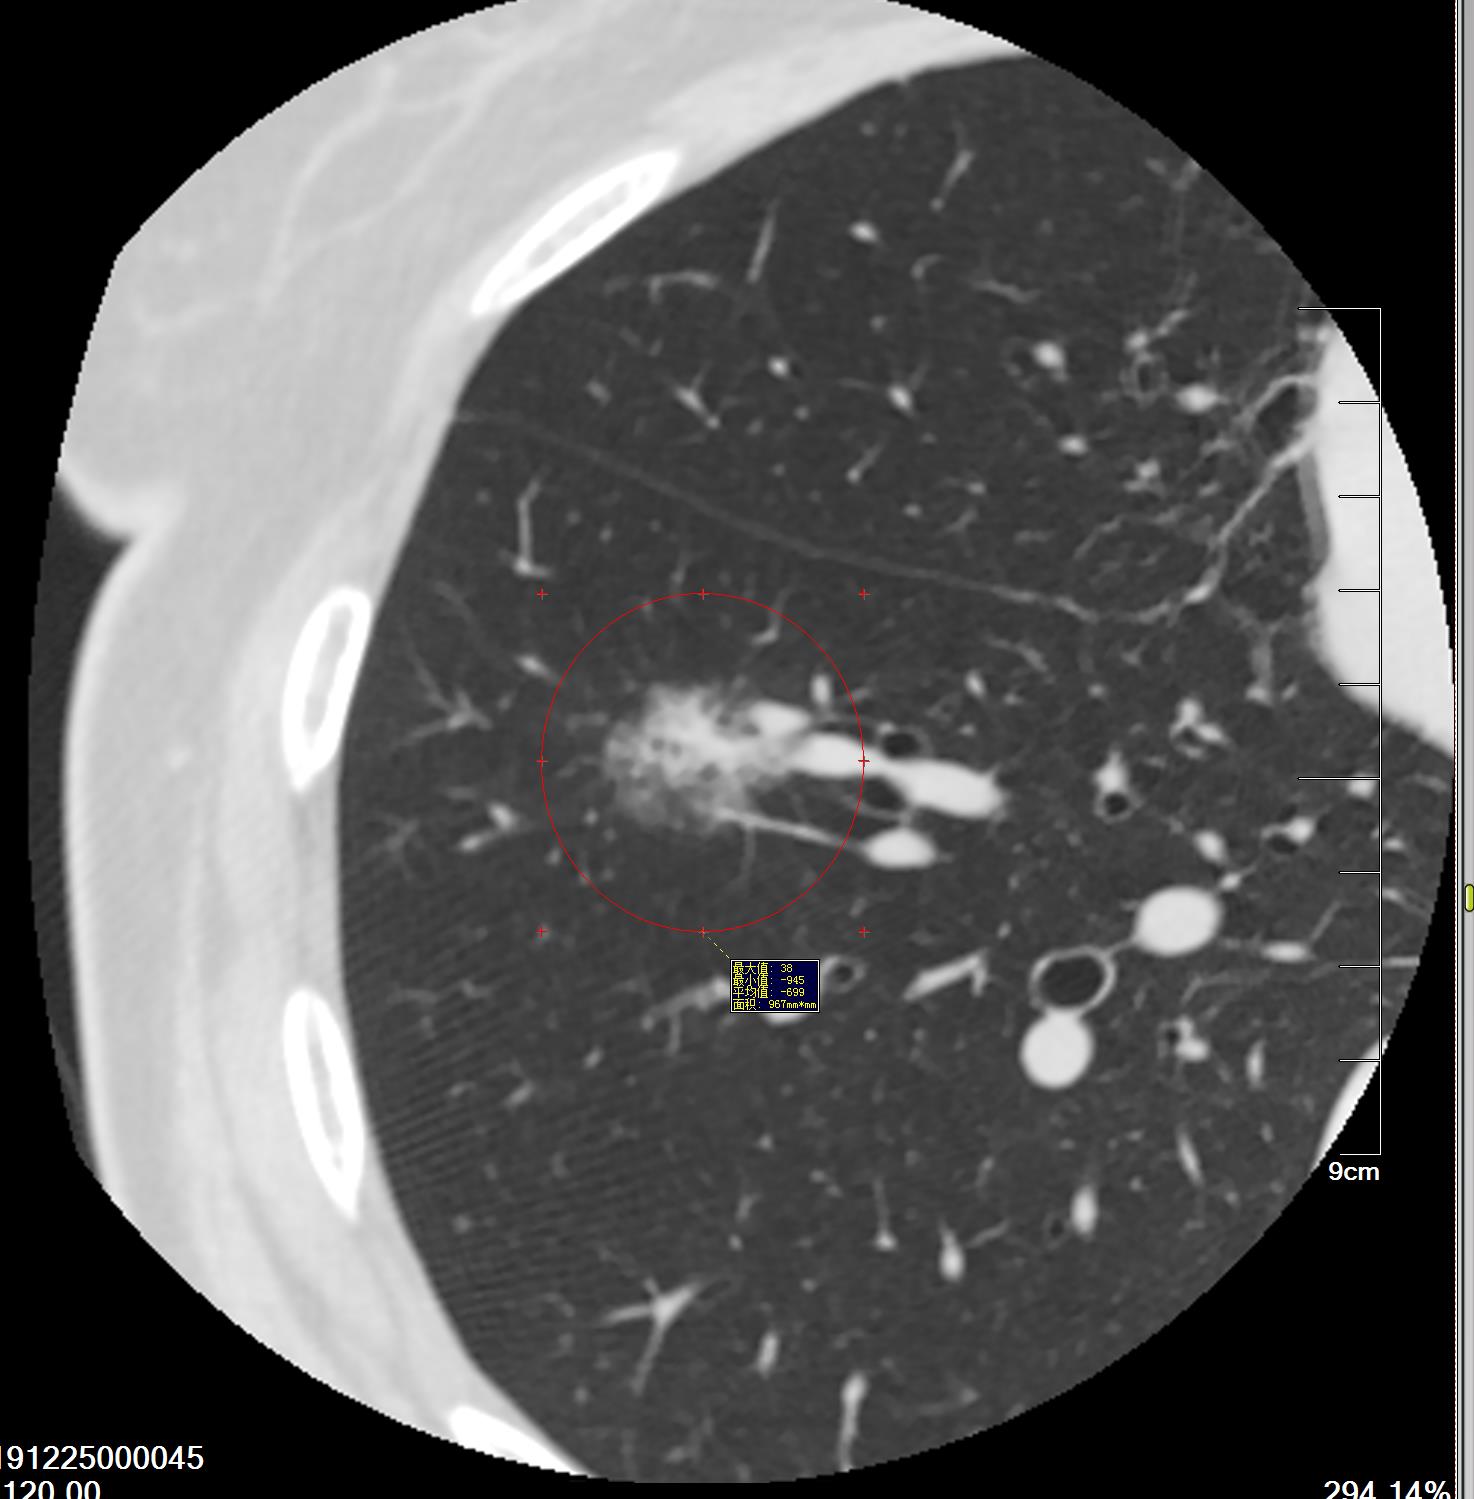

图1、2004年

图2、3 2008年1月10日

图4 2015年4月29日

图5、6 2020年5月15日

漫长的16年,一个纯磨玻璃结节从原位腺癌缓慢正常到浸润性腺癌早期阶段(影像估测),所以说纯磨玻璃结节是不可怕的,可以安心随访,到合适的时机手术完全来得及,不要上来动不动就手术,动不动就消融!